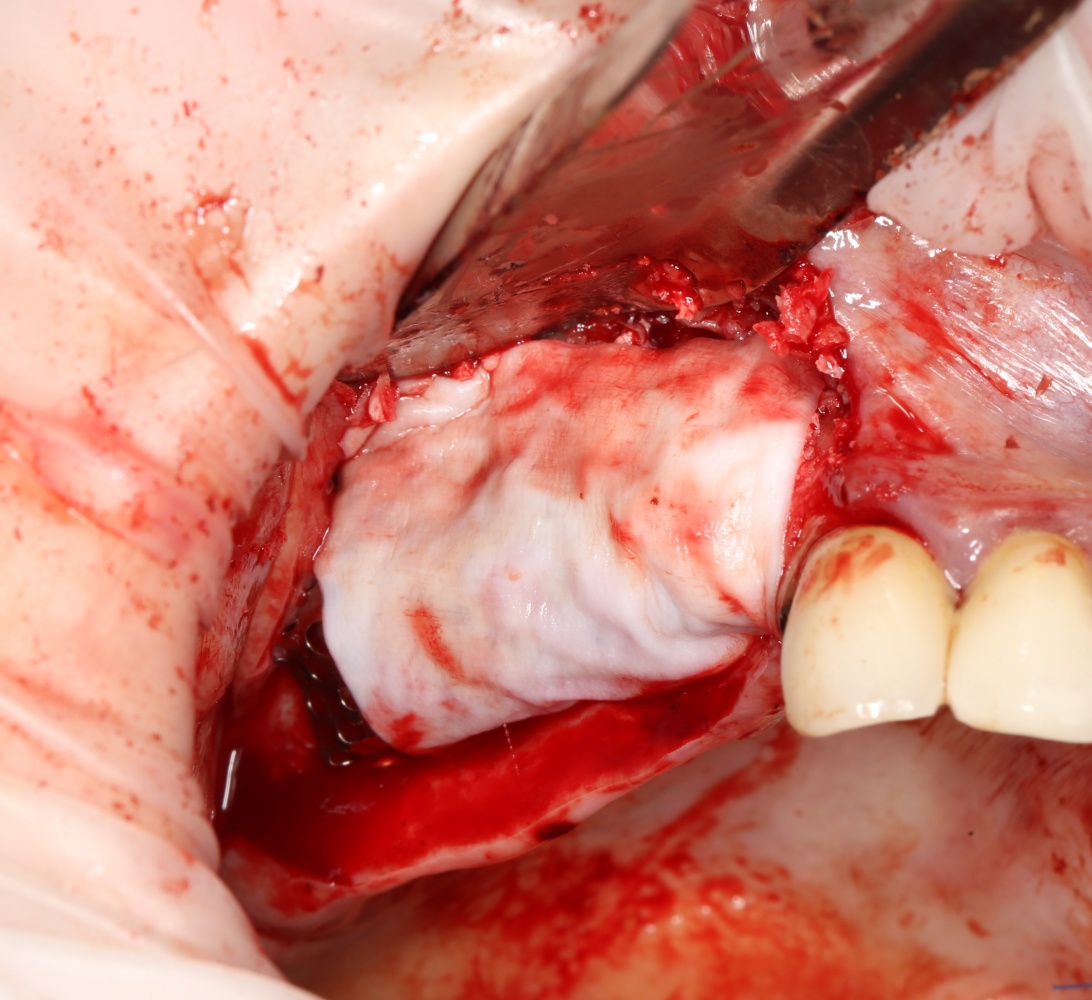

Я же в своей практике для создания доступа использую ультразвук, а именно — электрический пьезохирургический аппарат VarioSurg (NSK). Он позволяет делать очень красивый и практичный доступ любой формы:

Однако, почему я выбрал именно этот способ? Плюсы:

- это более безопасно, нежели использование бормашины.

- можно сделать доступ любой формы.

- после создания доступа получается костный фрагмент, который мы можем использовать по-разному (для закрытия перфорации, костной пластики,

- можно создавать большие доступы и закрывать их получившимся костный фрагментом, легко обходить септы, шипы и перегородки дна верхнечелюстной полости

- сам процесс создания доступа получается более контролируемым.